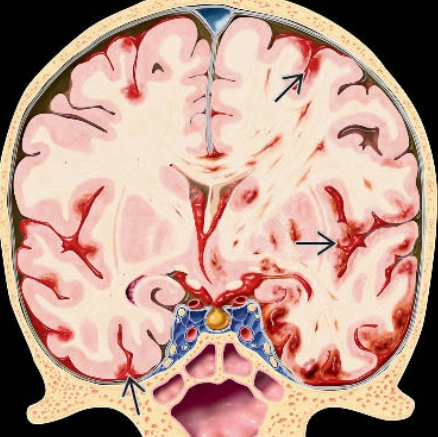

Dập não (Cerebral Contusion)